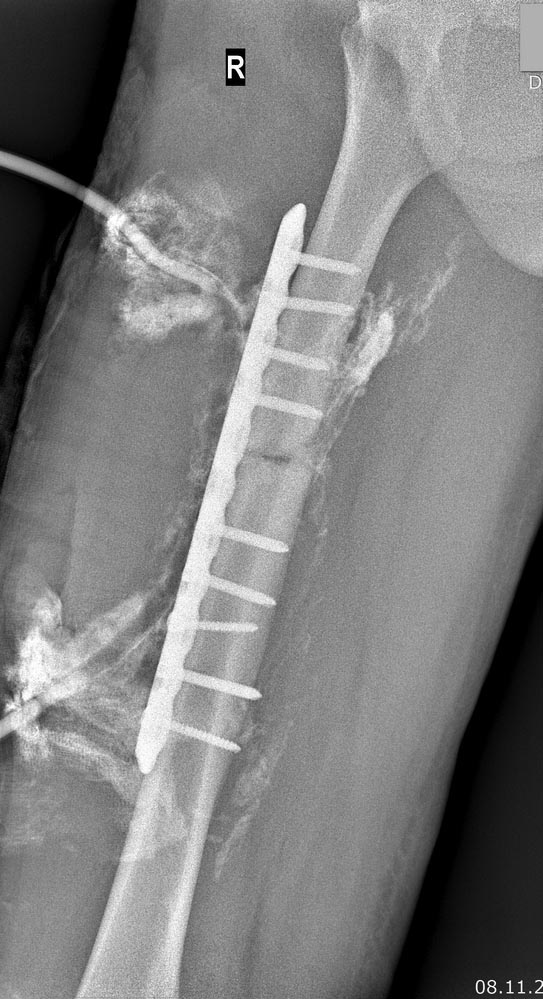

несращение и остеомиелит бедра |

Коллеги, просьба Вашего мнения по тактике.Пациент 45 лет, без значимых сопутствующих. В середине октября 2017 – ДТП, оперирован по месту ДТП. Первичных снимков не предоставил. Через 2 недели - картина глубокой флегмоны правого бедра. Фистулография после первичного дренирования флегмоны – см вложение. При ревизии выявлено, что не менее 3/4 окружности диафиза бедра скелетированы по всему длиннику пластины, А на уровне проксимального отломка на протяжении не менее 6-7 см – циркулярное скелетирование. Пластина удалена. АНЧКФ. При ревизии раны по медиальной поверхности диафиза бедра выявлена массивная нагноившаяся гематома, при эвакуации которой выявлено арозивное кровотечение из ветви глубокой артерии бедра. Тампонада с использованием гемостатических губок. Продолжающегося кровотечения не было. Ведение раны на вакуумных повязках. Вторичный ранний послойный шов. Дренирование редон-дренажами с промыванием антисептиком в связи с продолжающимся детритным отделяемым до чистых вод в течение около 2,5 недель. Компрессия на АНЧКФ. Минимально выраженные проявления инфекции мягких тканей проксимальных стержней, контролируемые местной обработкой. В конце декабря – вскрытие и дренирование инфицированной подкожной гематомы п/о рубца на уровне проксимальных винтов, достоверных данных о связи с внутрикостным процессом получено не было (УЗИ, фистула). В динамике по Рг и МСКТ: признаков консолидации нет, выявлен внутриканально интерпонирующий зону перелома фрагмент кортикальной кости, формирование внутриканальных секвестров в местах стояния винтов Шанца, что более оформлено в проксимальном отломке. В настоящее время места стояния стержней и спиц без признаков инфекции. Персистирующий диффузный отек медиальной поверхности бедра при вертикализации. СОЭ 20-30, СРБ 15-20. Вложение: фистулография в начале, Рг-контроль, внешний вид, выборка МСКТ от 20.02.18 в jpeg по ссылке